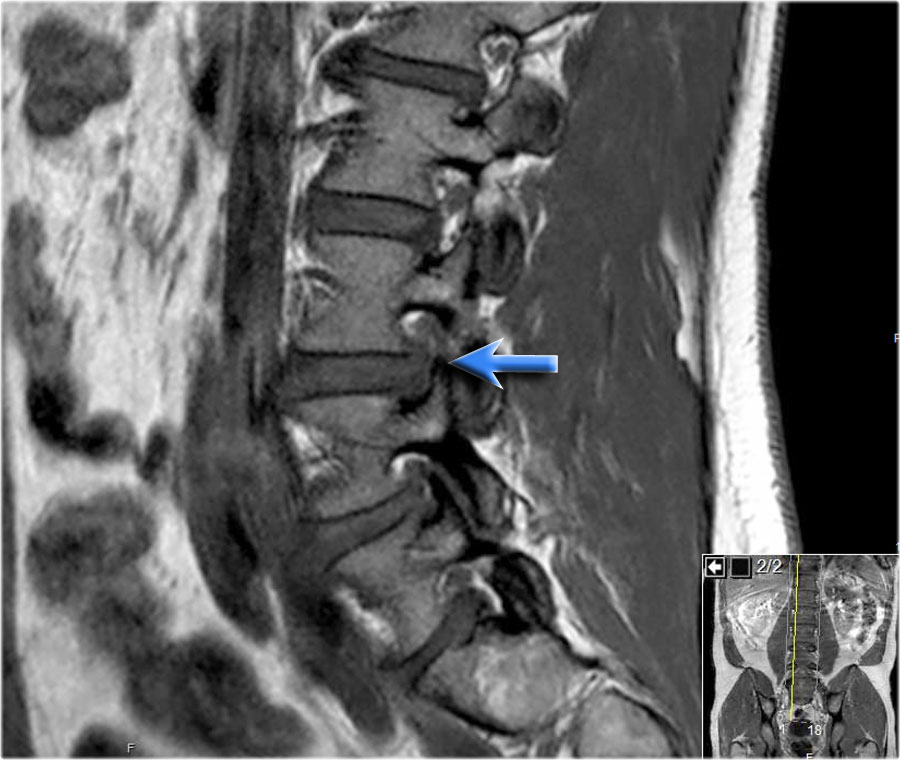

Hình ảnh chuỗi xung T1W mặt phẳng đứng dọc cho thấy một cấu trúc giảm tín hiệu rất thấp tại mức L4L5 (mũi tên) và tại mức L5S1.

Tiếp tục xem các hình ảnh chuỗi xung T2W.

Trên chuỗi xung T2W, cường độ tín hiệu cũng rất thấp.

Chụp CT được thực hiện để xác định liệu đây có phải là đĩa đệm thoát vị bị vôi hóa hay một xảo ảnh nào đó.

Tiếp tục xem các hình ảnh CT.

Tín hiệu thấp cuối cùng được giải thích là do hiện tượng chân không (vacuum phenomenon) gây ra bởi khí nitơ trong đĩa đệm thoát vị tại cả mức L4L5 (mũi tên đỏ) và mức L5S1 (mũi tên xanh dương).

Trước tiên hãy cuộn qua các hình ảnh chuỗi xung T1W mặt phẳng đứng dọc này.

Các dấu hiệu là gì?